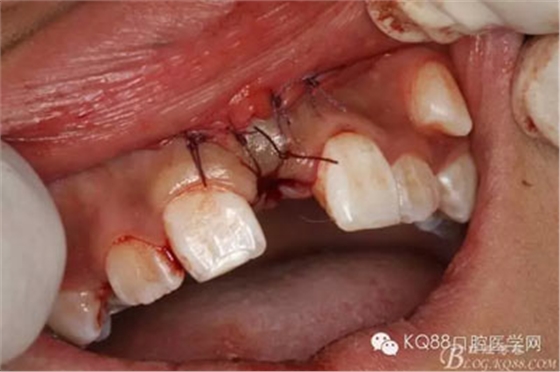

圖14.拔除的倒置多生牙,牙冠還是比較大

圖15.拔除多生牙后,清理牙槽窩的骨碎片

圖16.牙槽窩內(nèi)放膠質(zhì)銀一枚